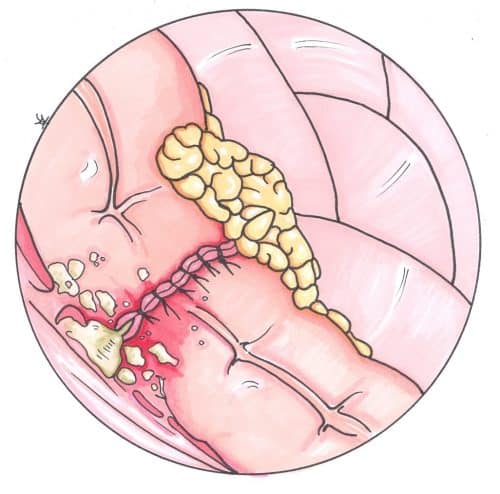

Patients who are systemically unwell, signs of pertonism, and/or with large leaks will require surgical intervention to ensure appropriate source control. This will typically require a laparotomy, washout of the contamination, and refashioning of the anastomosis and/or formation of a defunctioning proximal stoma.

Figure 2 – A hand-sewn anastomosis of the sigmoid colon